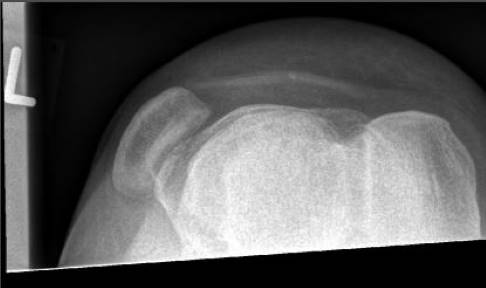

Ein ausführliches Arzt-Patienten-Gespräch und eine genaue körperliche Untersuchung sind Grundvoraussetzungen für eine erfolgreiche Behandlung. Röntgenaufnahmen des Kniegelenks geben Hinweise auf mögliche anlagebedingte Ursachen für die Luxation und zeigen knöcherne Verletzungen. Anhand von Aufnahmen der Patella in zunehmender Beugung (Defilee-Aufnahme) kann der Arzt die Verschiebung der Kniescheibe beurteilen. Zusätzlich erkennt er eventuelle Chondropathien (Knorpelschäden).

Diagnose der Patellaluxation